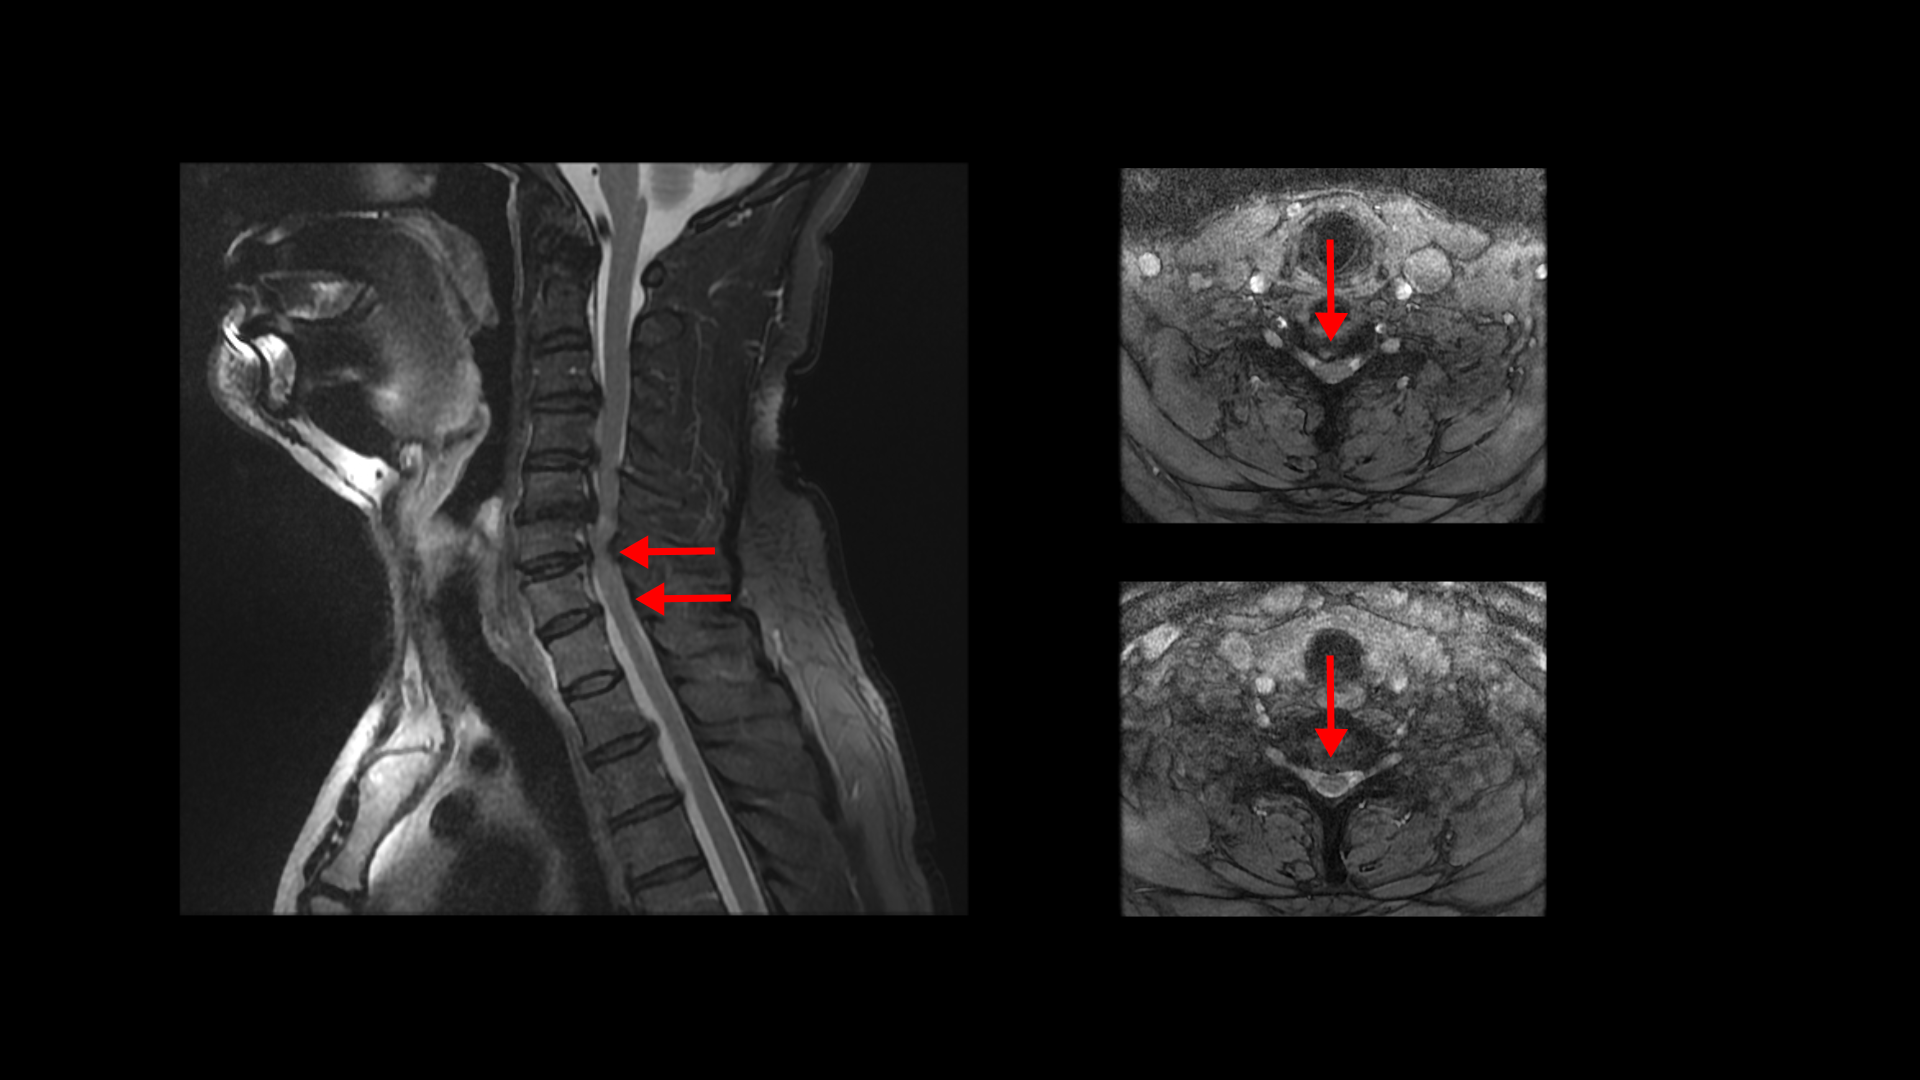

이분 MRI에서 보시다시피 전체적으로 목의 한마디만 제외하고 여러 마디가 다 안 좋습니다.

목의 3번 4번과 4번 5번에는 가운데 쪽으로 디스크 돌출이 있고

5번 6번 문제가 제일 심각한데, 가운데 우측으로 목디스크 파열이 심하게 있습니다.

오른쪽으로 보시다시피 신경 나가는 길이 디스크와 협착으로 많이 막혀 있고 척수 신경에는 경추척수증, 즉 척수신경의 손상이 보입니다.

6번 7번과 7번 흉추 1번 디스크도 가운데로 밀려 나와있습니다.